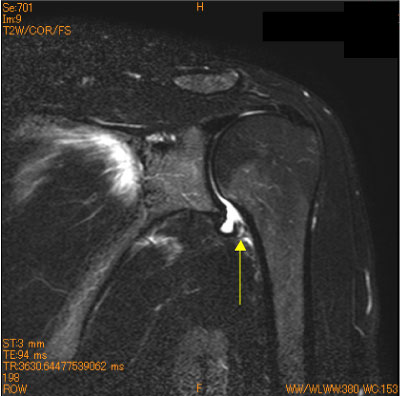

HAGL(humeral avulsion glenohumeral ligament)

40代女性。反復性脱臼肩、スキー歴(+)。

中高年の症例では、腱板断裂やHAGL(humeral avulsion glenohumeral ligament)の有無をcheckする必要(+)

![]() Obl. Cor T2WI 脂肪抑制 |